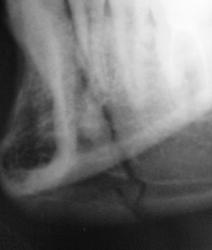

Выяснение "отношений" продолжается.

Ваше мнение коллеги.

на мой взгляд здесь перелом суставного отростка